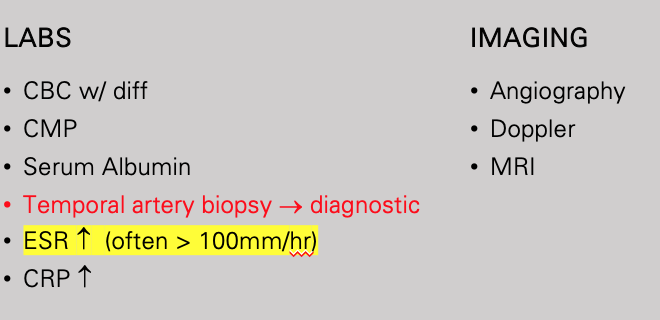

Aneurysm: arterial dilation

Diameter of that region is increased > 50% relative to normal aortic diameter

Normal diameter of the aorta at the level of the renal arteries is approximately 2.0 cm (range 1.4 to 3.0 cm) in most individuals

Diameter greater than 3.0 cm is generally considered aneurysmal

Aortic Aneurysm

Abdominal (aortic aneurysm) (AAA)

Thoracic

Ascending (aorta)

Aortic arch

Descending (aorta)

Most Common types of Aortic Aneurysms